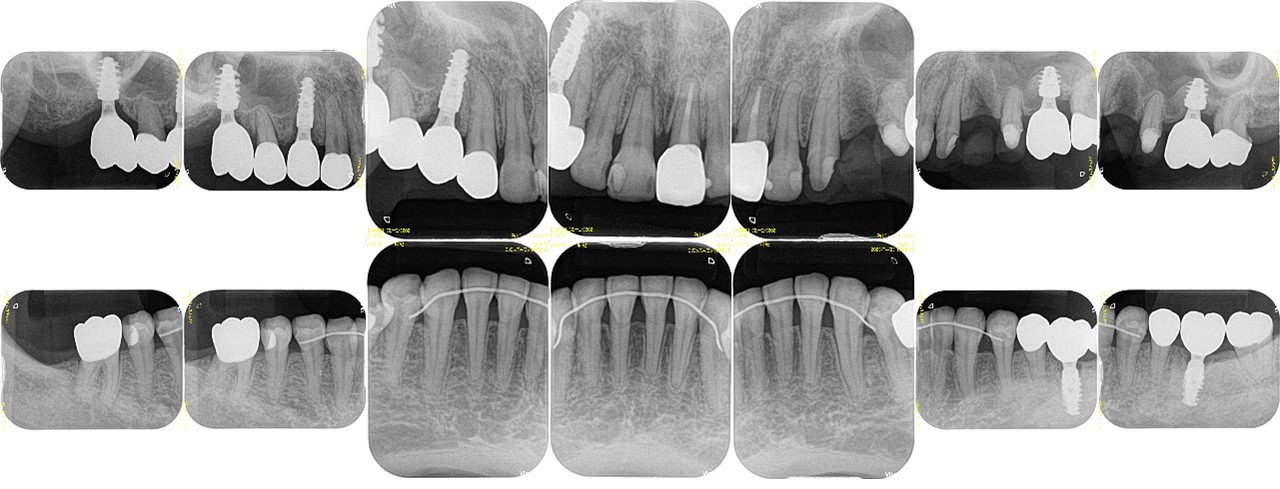

機能的な咀嚼障害を主訴に来院(図18・19)。咬合状態は不安定で、矯正治療を含めた全顎的な治療が必要と診断した。治療計画では右上4・6、左上4・6、左下6部に、それぞれインプラント治療を計画した。右上5、左上5は、隣在歯が近遠ともインプラント治療になるため感覚受容器が乏しくなることが予測されるため、歯髄の有無が大きく影響されやすい環境と判断した。

今回、インプラントを用いた咬合再構成症例を目指したため最終補綴設計は全て単冠処理することを計画し、インプラントが隣接する天然歯の状態は有髄の状態を目指した。右側上下5、左上3・5、左下5は、初診時の段階でう蝕が広範囲で進行していたためVPTを行った。左上4部に行ったインプラントのインテグレーションが不良であったため治療期間中に撤去し、再埋入予定のため左上3・5はプロビジョナル・レストレーションではあるが、VPTを行った5歯は有髄歯の状態で術前の補綴設計通り、単冠処理で治療が遂行している(図20〜26)。今後、万が一再介入の必要性が発生したとしても、今回単冠処理で終了していることで、対応は比較的しやすい状態であると考える。

(図19)初診時のレントゲン所見

ほとんどが有髄歯であり無髄歯は左上1番と左下6番のみ左下6番は歯根破折しており抜歯を予定

(図26)術後レントゲン像

左上1番以外は天然歯は全て有髄歯の状態で保存できている